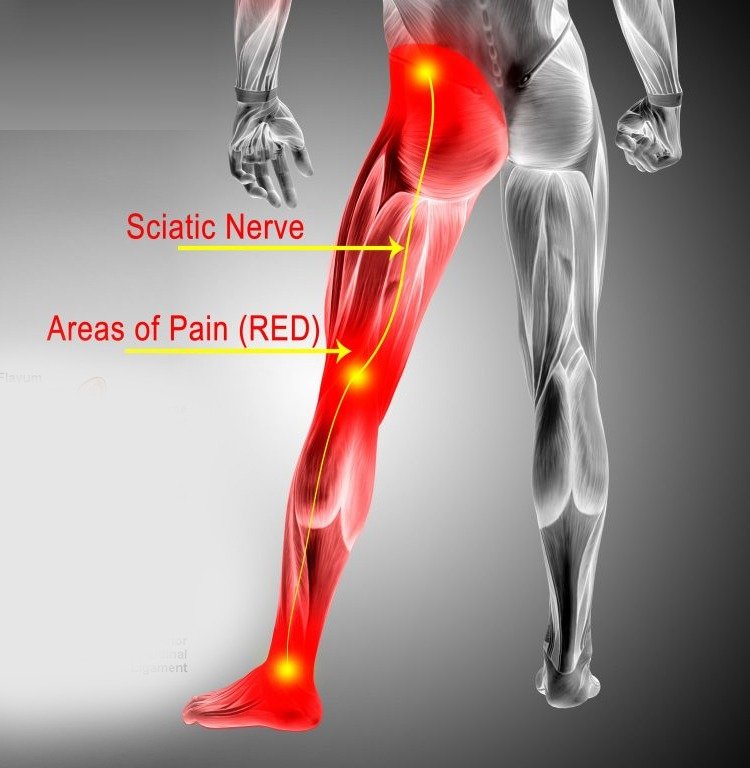

هو حالة طبية بسبب ضغط أو التهاب العصب الوركي. يمتد هذا العصب من الظهر للفخذ والقدم.

الأعراض تتضمن ألم شديد في الظهر والساق. قد تشعر بالتنميل والوخز كذلك. صعوبة في الحركة والقيام بالمهام اليومية أيضا.